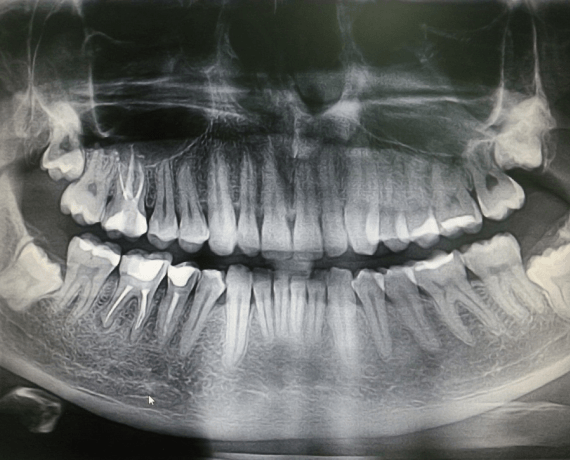

Фотографии ортопантомограмм и работ Родена